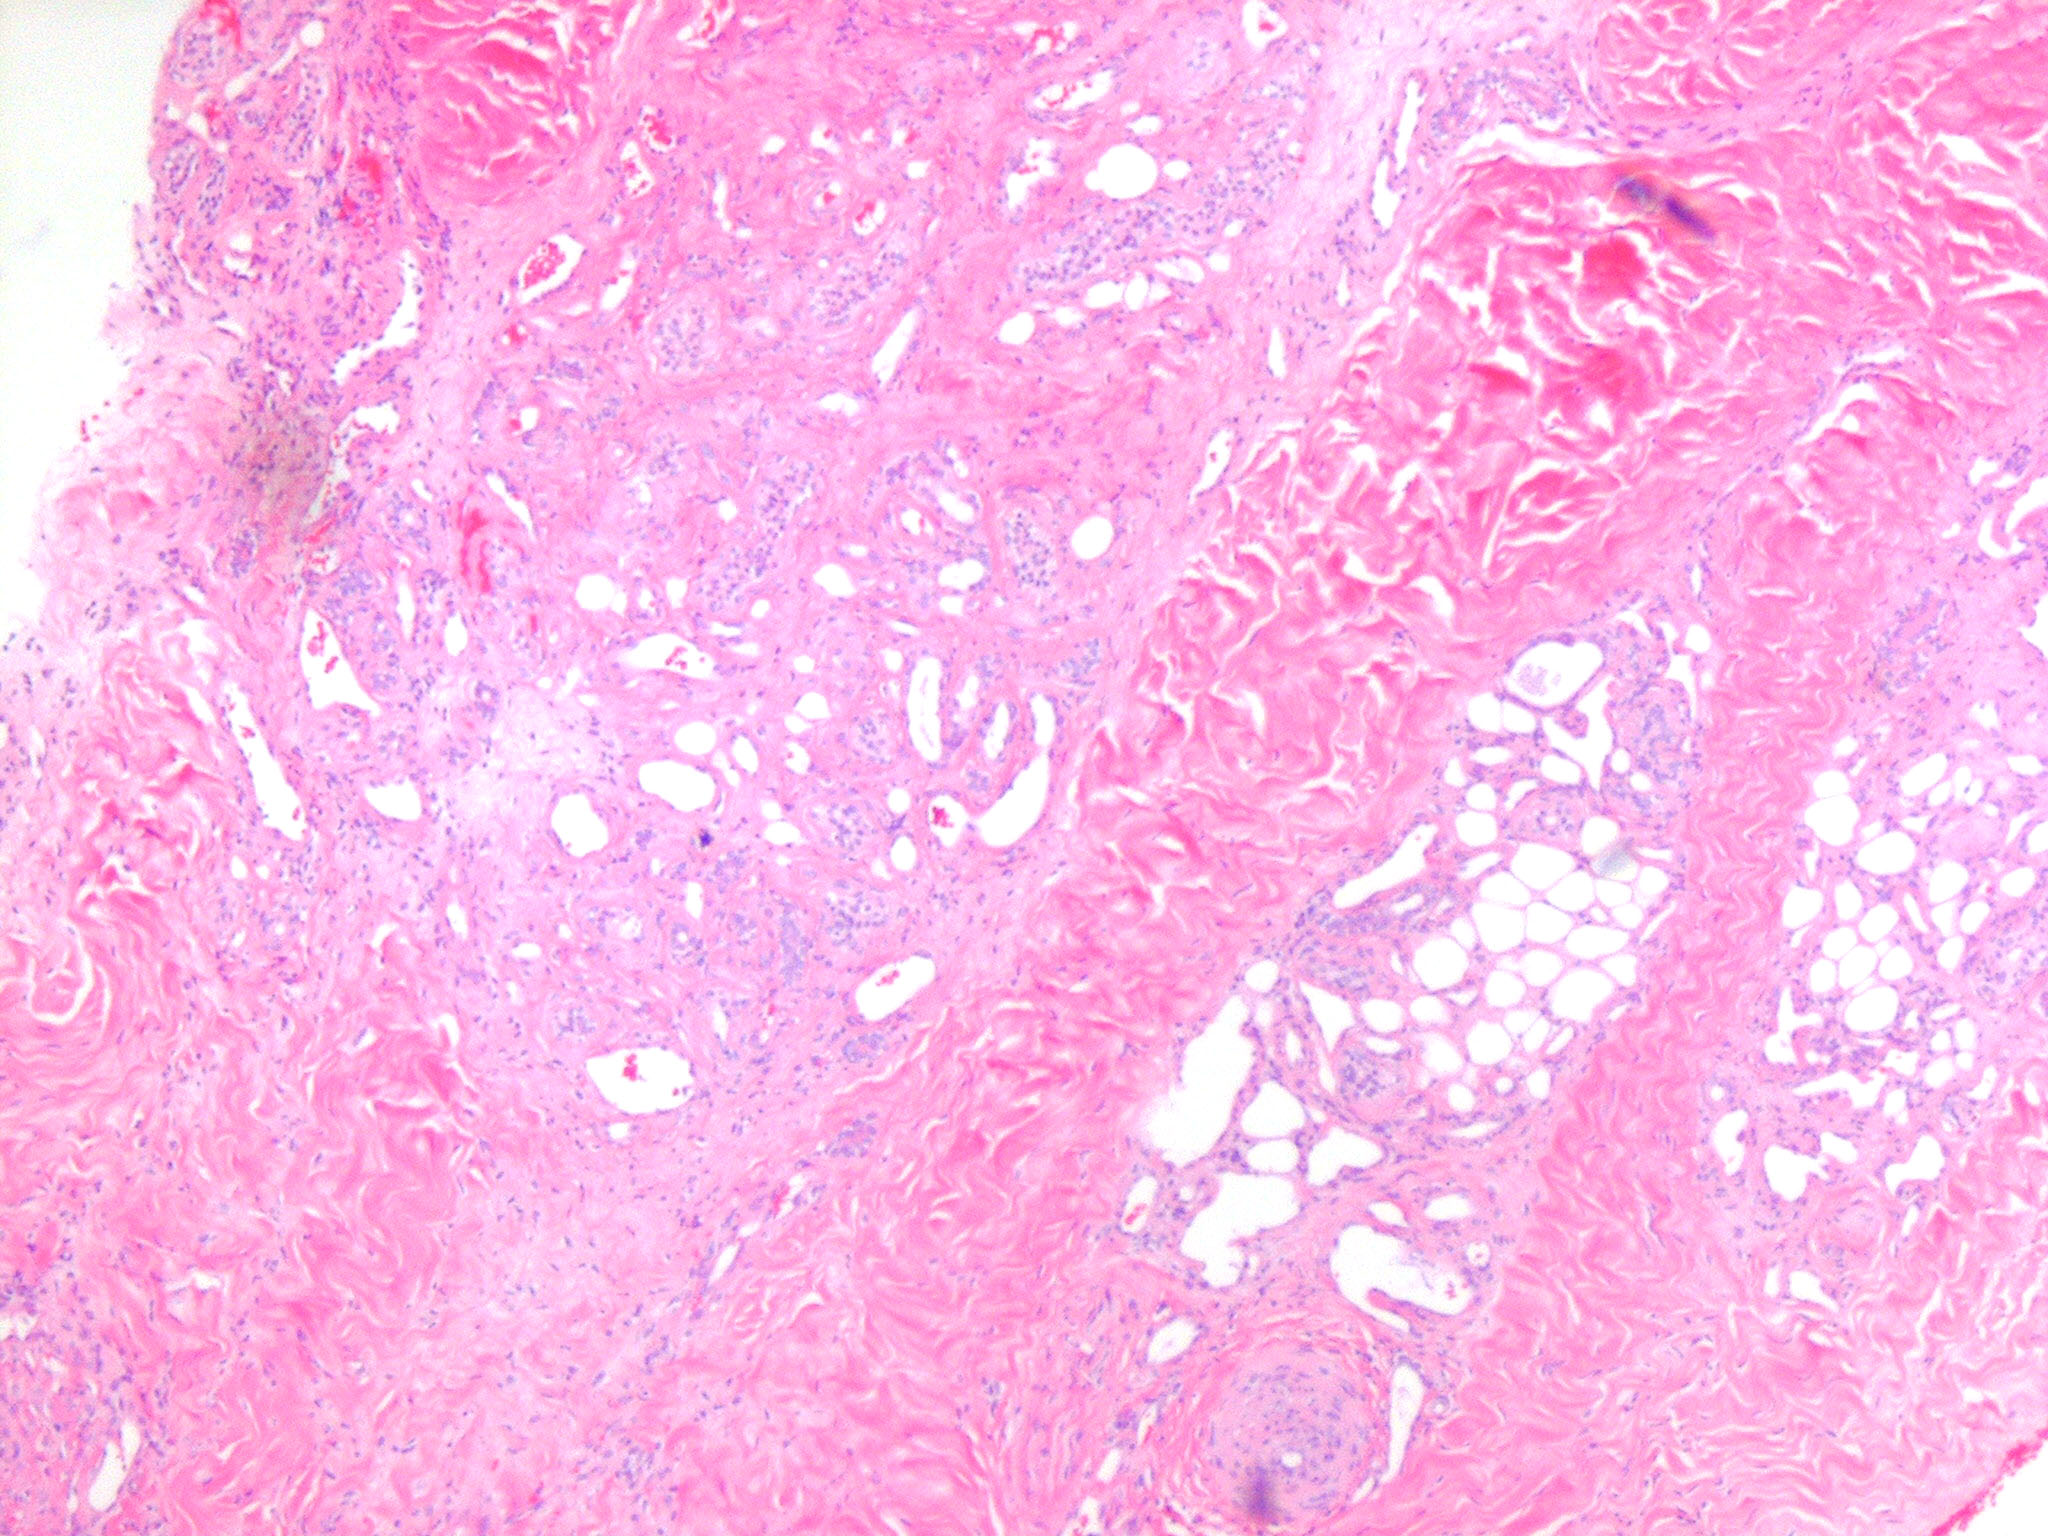

Eccrine angiomatous hamartoma = ورم عجائبي وعائي وناتح

OLYMPUS DIGITAL CAMERA